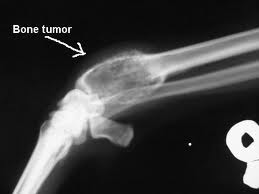

Bone cancer Part 3

In addition to bone cancer, there are various types of benign bone tumors. These include osteoid osteoma, osteoblastoma, osteochondroma, enchondroma, chondromyxoid fibroma, aneurysmal bone cyst, unicameral bone cyst, and giant cell tumor (which has the potential to become malignant). As with other types of benign tumors, these are not cancerous. Continue reading

Bone cancer Part 2

A tumor is a collection of abnormal cells grouped together. However, not all tumors are cancerous. A tumor can be benign (not cancerous) or malignant (cancerous). Benign tumors are usually less dangerous and are not able to spread to other parts of the body. Benign tumors can still be dangerous. They can continue to grow and expand locally. This can lead to compression and damage to the surrounding structures. Malignant tumors are usually more serious and can spread to other areas in the body. Continue reading

Bone cancer Part 1

Bone cancer facts

• The majority of cancer involving the bones is metastatic disease from other remote cancers. Primary bone cancer is much rarer.

• Not all bone tumors are cancerous.

• The most common symptom of bone cancer is pain. The pain is usually mild initially and gradually becomes more intense.

• Treatment of bone cancer includes a combination of surgery, chemotherapy, and radiation therapy.

• Treatment is based on the size and location of the cancer and whether or not the cancer has spread from the bone to surrounding tissues. Continue reading